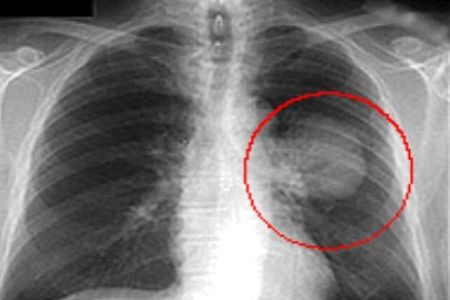

Lorsque, sur la base des douleurs et des caractéristiques du patient, un médecin estime qu’il est question de cancer du poumon, le patient est généralement soumis en premier lieu à une radiographie de la cage thoracique.

Radiographie sur laquelle une tumeur est visible

Il s’ensuit en cas de besoin un CT-scan, lequel fournit entre autres des informations sur la taille, les métastases et les caractéristiques de la tumeur.